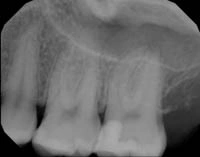

Before and After